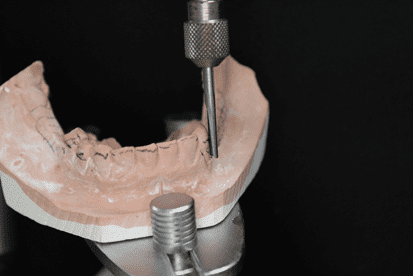

A 49-year-old female patient attended the prosthesis clinic at Nilton Lins University, mentioning dissatisfaction with her total obturator prosthesis, because she had a “broken front tooth” and the prosthesis was “falling”, emphasizing the desire to maintain the shape of the same. In the anamnesis reported that previously in 2012 he was diagnosed with mucoepidermoid carcinoma of intermediate degree in the palate (Appendix 1) and in 2013 after performing surgical removal and performing new tests, who did not indicate the presence of malignancy (Appendix 2), was attested as cured, besides being hypertensive and using the drugs losartan potassium 50 mg twice daily and levanlodipine besidate 2.5 mg once a day. No alterations were observed on extraoral clinical examination. In the intraoral clinical examination, there was absence of the upper arch teeth, bucosinusal communication and partial maxillary edge and in the lower region only the presence of teeth 31, 32, 33, 41, 42, 43, 44 and 45 (figures 1 and 2).

Figure 1: Surgical defect of the upper arch.

Subsequently, the anatomical molding of the lower arch was produced with alginate (Jeltrate dustless®, Dentsply, Argentina) (figure 12) and succeeded by the preparation of the study model in type IV plaster (Durone®, Dentsply, Argentina) and design (figure 13). In the latter, the circumferential clamps were chosen in teeth 44 and 45, and, t-staple in tooth 33, the lingual bar was selected as the larger connector. After this, mouth II was prepared, the niches were made and the molding of work with condensation silicone (Zetaplus®, Zhermack, Italy) (figure 14), which was sent to the laboratory for the purpose of casting the metal frame. After adapting to the model, the orientation plan with pink 7 wax was developed, making the necessary adjustments.

The mold was removed with slight movements, prompting the patient to move the mime muscles (figure 28). Immediately after molding, the mold was filled with type IV plaster (Durone®, Dentsply, Argentina) to obtain the facial model. With the aid of a vibrator, the plaster was deposited on the mold to prevent the formation of bubbles and when taking prey, the model was removed, so the finishes were executed (figure 29). Subsequent surgical removals, the treatment plan of choice was radiotherapy, being performed for two months, where it has already begun and is under medical follow-up.

Figure 29: Model of the finished face.